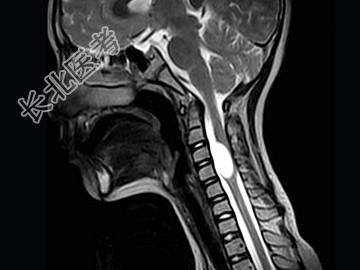

- 单项选择题女,9岁, 颈部疼痛、活动受限2个月,MRI检查如图, 最可能的诊断为 ( )